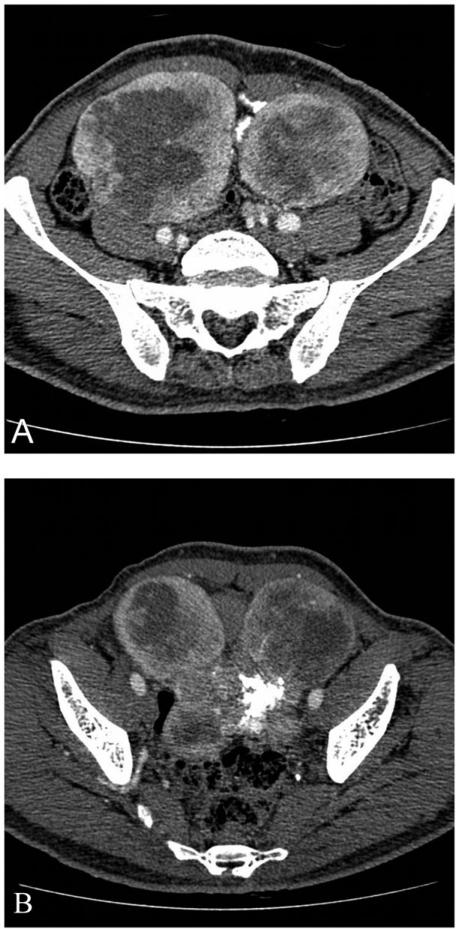

Solitary fibrous tumours are rare spindle cell tumours that generally arise from the pleura but on rare occasions arise in other locations such as the head and neck region, stomach and retroperitoneum. Very few reports exist on the imaging findings of these tumours in extra pleural sites such as the mesentery. We report the computed tomography (CT) imaging findings of a rare case of solitary fibrous tumour in a 68-year-old man who presented with a slowly enlarging painless pelvic mass. CT scan showed a well-defined, multilobulated, highly vascular pelvic mass with dense calcifications and central hypoatteunating areas arising from the mesentery.

孤立性纤维瘤是一种罕见的梭形细胞肿瘤,通常起源于胸膜,但在极少数情况下也可发生于头部和颈部、胃和腹膜后等其他部位。关于这些肿瘤在胸膜外部位(如肠系膜)的影像学表现,仅有少数报道。我们报告了一例罕见的 68 岁男性孤立性纤维瘤的计算机断层扫描(CT)影像学表现,该患者表现为逐渐增大的无痛性盆腔肿块。CT 扫描显示一个边界清楚、多叶状、高度血管化的盆腔肿块,伴有致密的钙化和源于肠系膜的中央低衰减区。